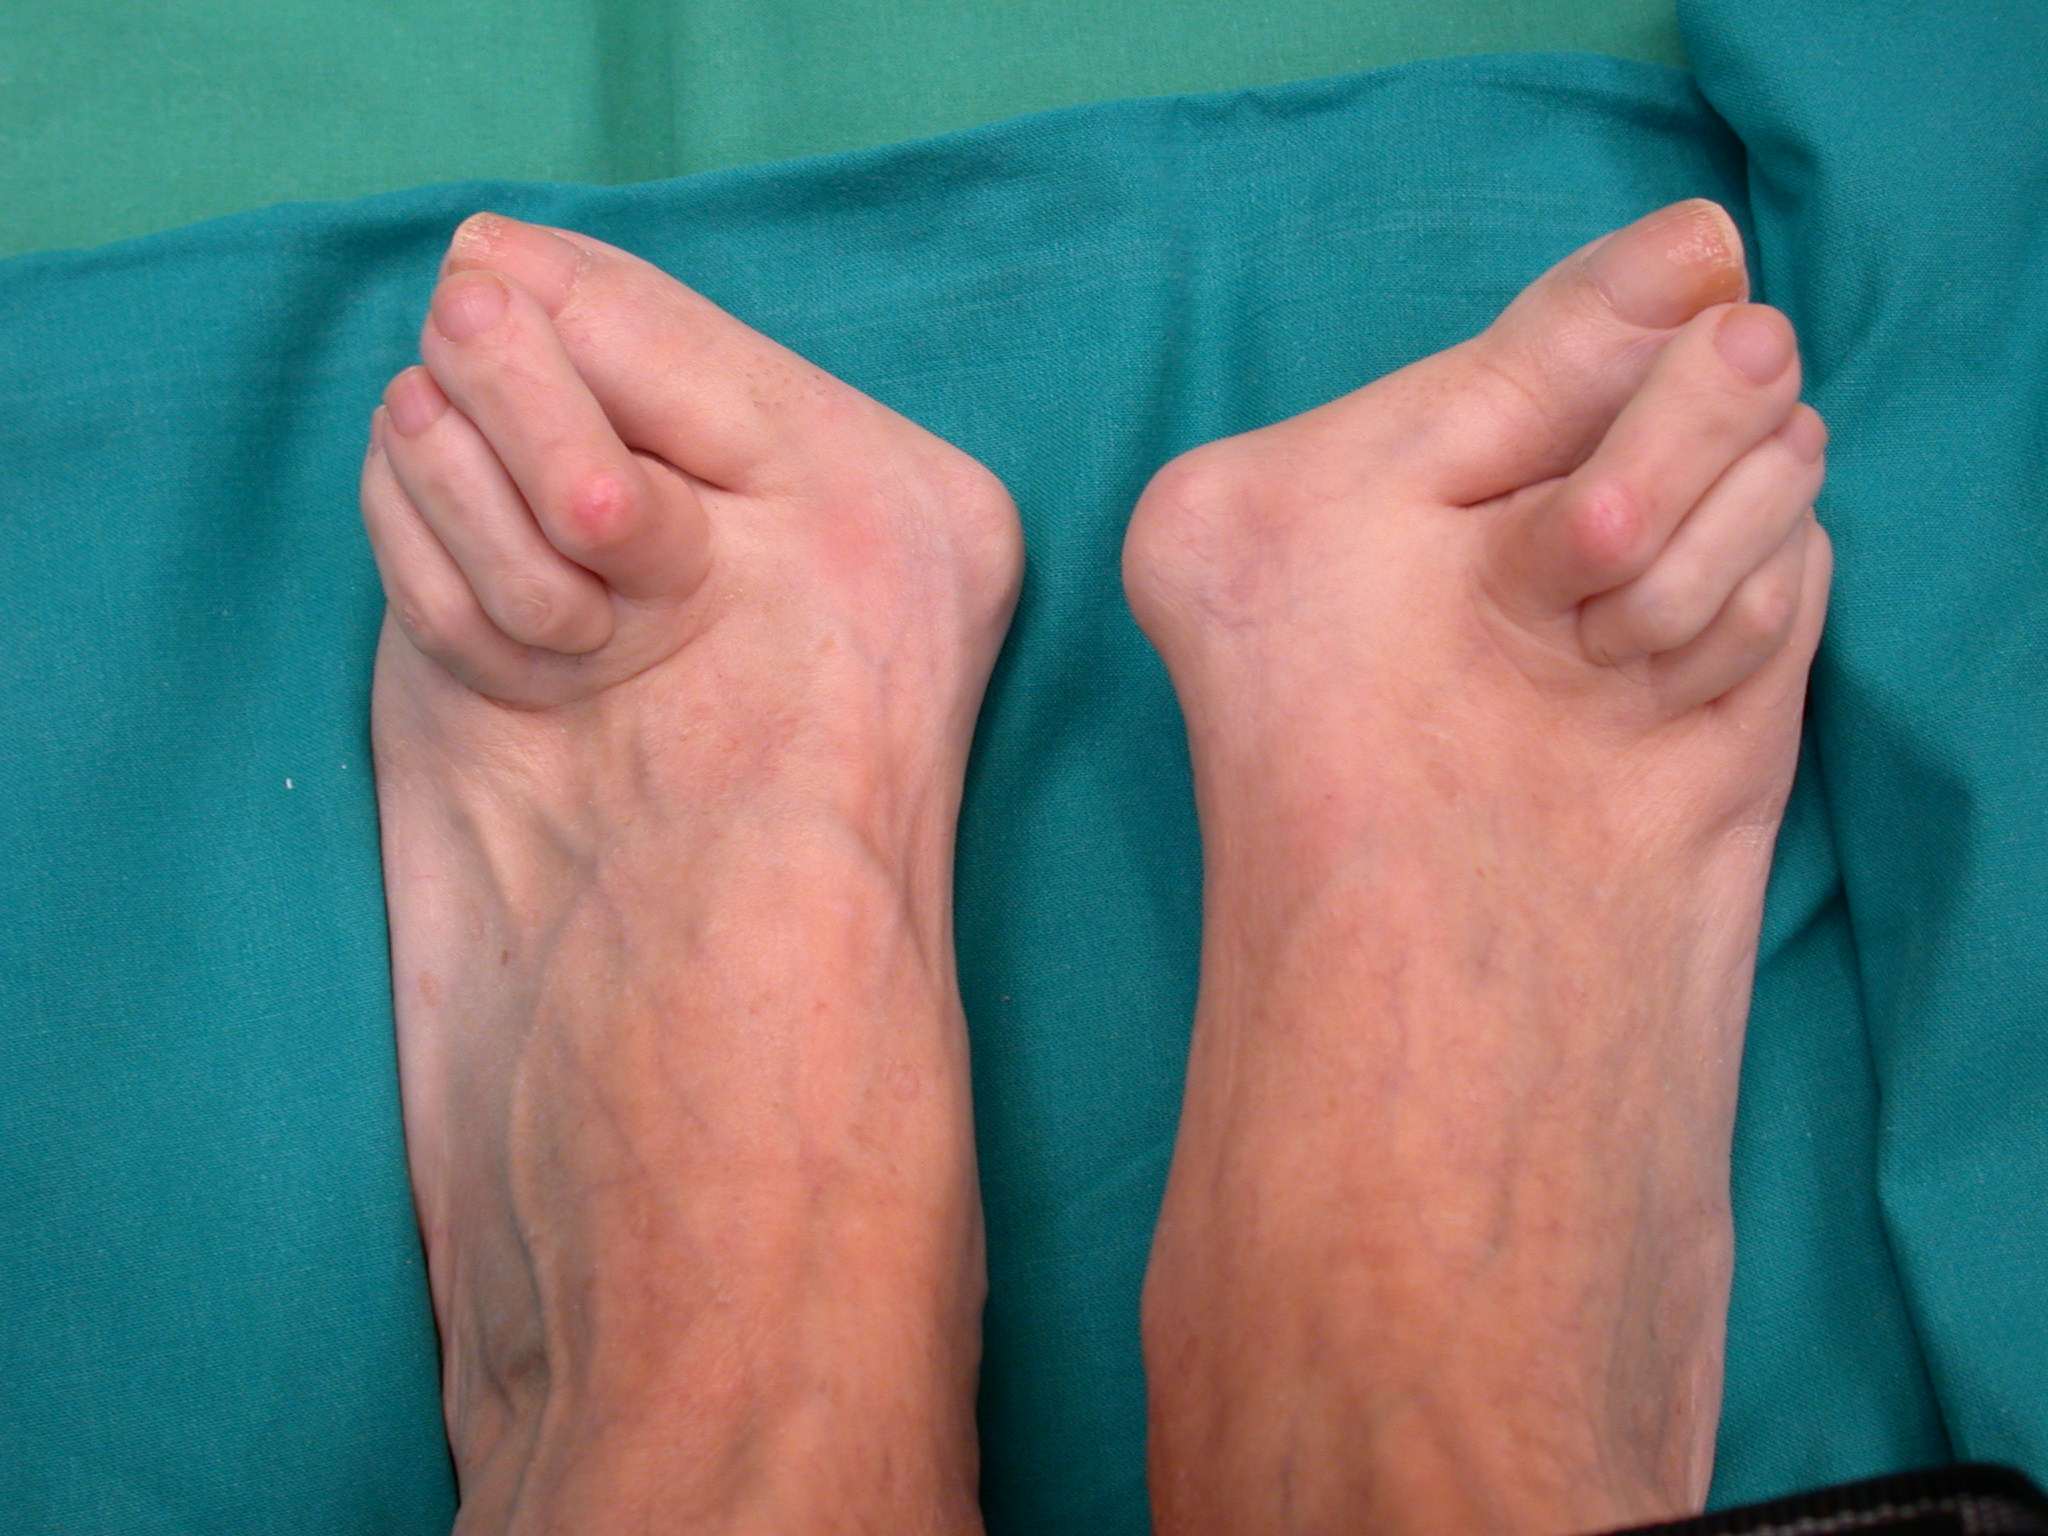

Tipicamente l’esordio è caratterizzato da dolori articolari accompagnati da tumefazione e rigidità che interessano le articolazioni di mani e piedi in maniera simmetrica ed aggiuntiva (cioè interessamento di altre articolazioni senza regressione nelle sedi già colpite). A livello del piede le articolazioni più frequentemente interessate sono le metatarso-falangee cioè le articolazioni alla base delle dita che vanno spesso incontro a lussazione patologica ; con minor frequenza sono interessate le articolazioni del retropiede e della caviglia (tra astragalo e scafoide , tra astragalo e calcagno, tibiotarsica). Se non adeguatamente trattata compaiono ipertrofia sinoviale ed erosioni dei capi articolari che comportano caratteristiche deformità ; in particolare all’avampiede si realizza spesso deformità in valgismo (cioè verso l’esterno) dell’alluce e delle dita laterali. Al retropiede il problema più comune è la comparsa di un progressivo piattismo che può arrivare a situazioni molto gravi per instabilità delle articolazioni interessati e per progressivo cedimento delle strutture tendinee , in particolare del tibiale posteriore.